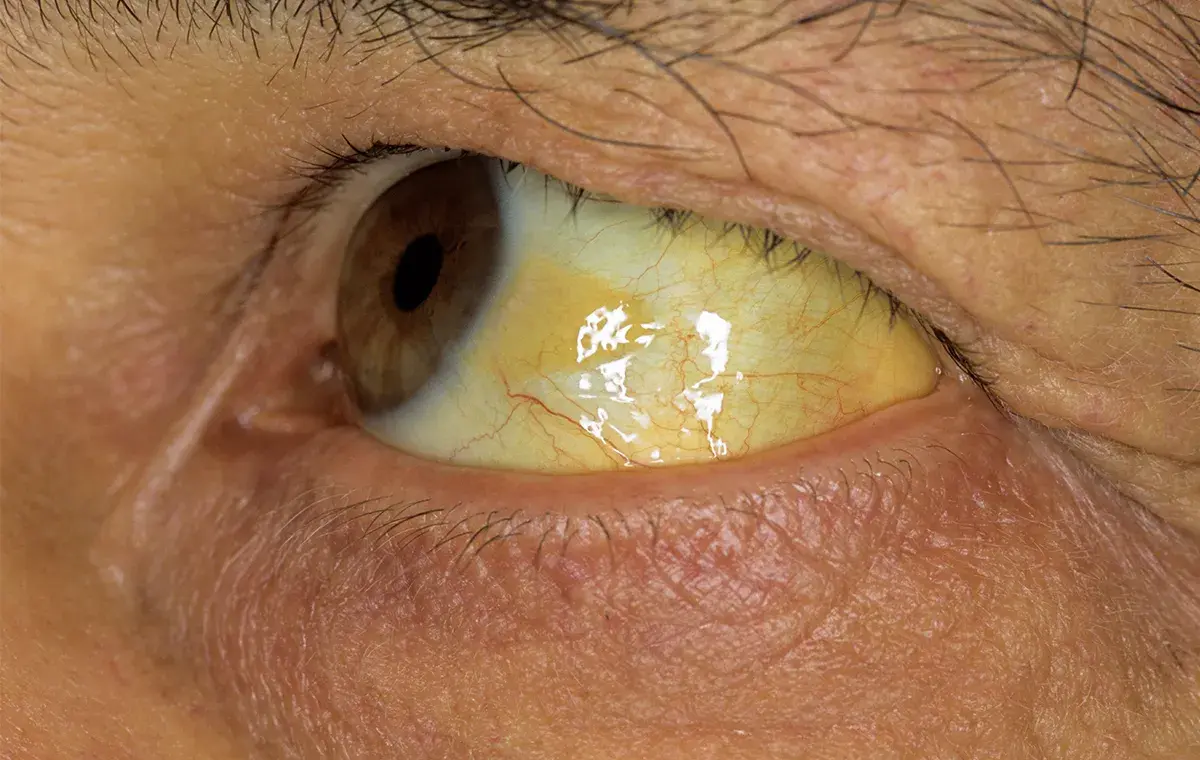

هپاتیت B یک عفونت ویروسی کبدی است که توسط ویروس هپاتیت B (HBV) ایجاد میشود. این ویروس میتواند بیماری را به شکل حاد (کوتاهمدت) یا مزمن (بلندمدت) ایجاد کند. بسیاری از افراد در مرحله حاد عفونت (بهخصوص کودکان) ممکن است هیچ علامتی نداشته باشند. اما عدهای دیگر پس از چند هفته از ورود ویروس دچار علائمی مانند زردی پوست و چشمها (یرقان)، خستگی شدید، تهوع، استفراغ، ادرار پررنگ و درد در ناحیه بالای شکم میشوند. این علائم معمولاً چند هفته طول میکشند و سپس بهبود مییابند. در موارد نادری هپاتیت B حاد میتواند آنقدر شدید شود که به نارسایی حاد کبد بینجامد که وضعیت بسیار وخیمی است.

- یکی از بارزترین علائم هپاتیت حاد یرقان است؛ یعنی زرد شدن پوست و چشمها که ناشی از بالا رفتن بیلیروبین در خون به دلیل اختلال عملکرد کبد است. ادرار تیرهرنگ و مدفوع کمرنگ نیز از علائم کلاسیک همراه با یرقان هستند